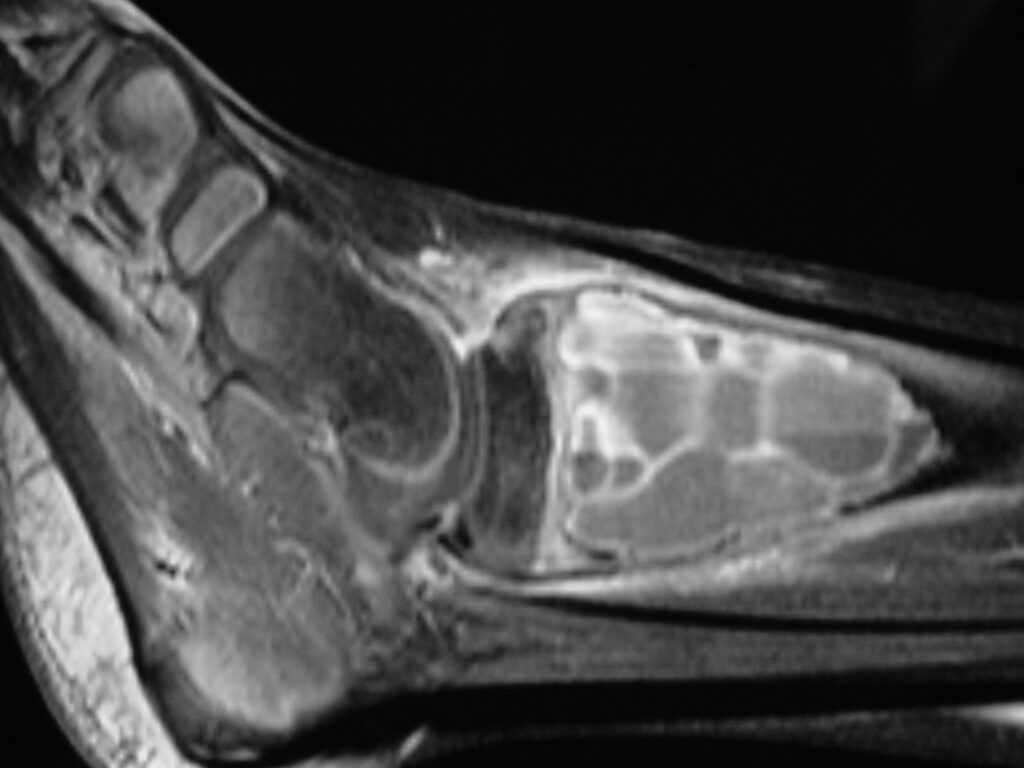

Fig 2 a-e. MRI of an ABC of Distal Tibia: Fig 2 a-c: geographic cystic expansile lesion with fluid-fluid levels. The fluid-fluid levels are caused by bleeding into the cavities. The blood collects and the degredation products settle to the gravity dependent areas of the cavities. This shows up as fluid-fluid levels on the MRI. Fig 2 d,e: This is a gadolinium enhanced MRI of the ABC of the distal tibia. There is peripheral and septal enhancement indication cyst formation. The contrast outlines the cystic cavities but does not enter into the center

Fig 2d: Coronal gadolinium enhanced MRI of an ABC

Fig 2e: Sagittal gadolinium enhanced MRI of an ABC